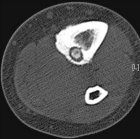

25 year old male with six months left shin pain that wakes him up at night, worse with activity, better with Aleve

Zoom image: Radiological image Radiological image.